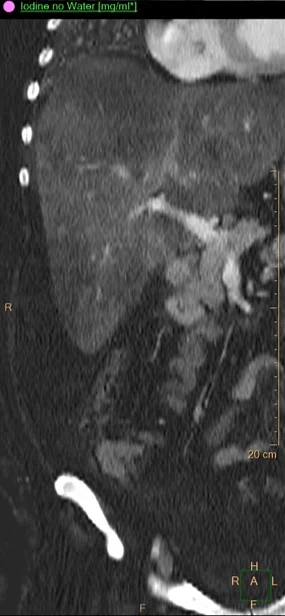

Iodine map: same as above. Notice the stalk.